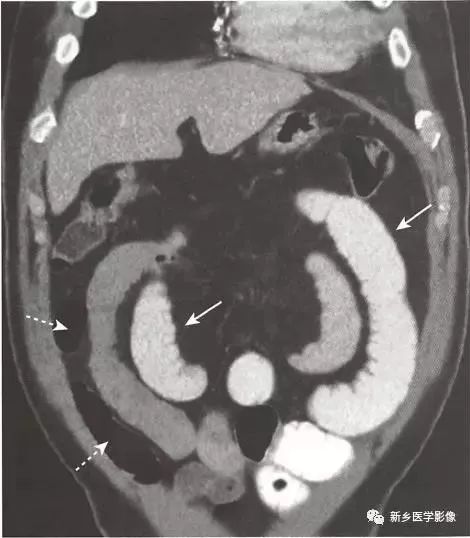

【经典影像】如何辨识肠梗阻

如何辨识肠梗阻经典影像?